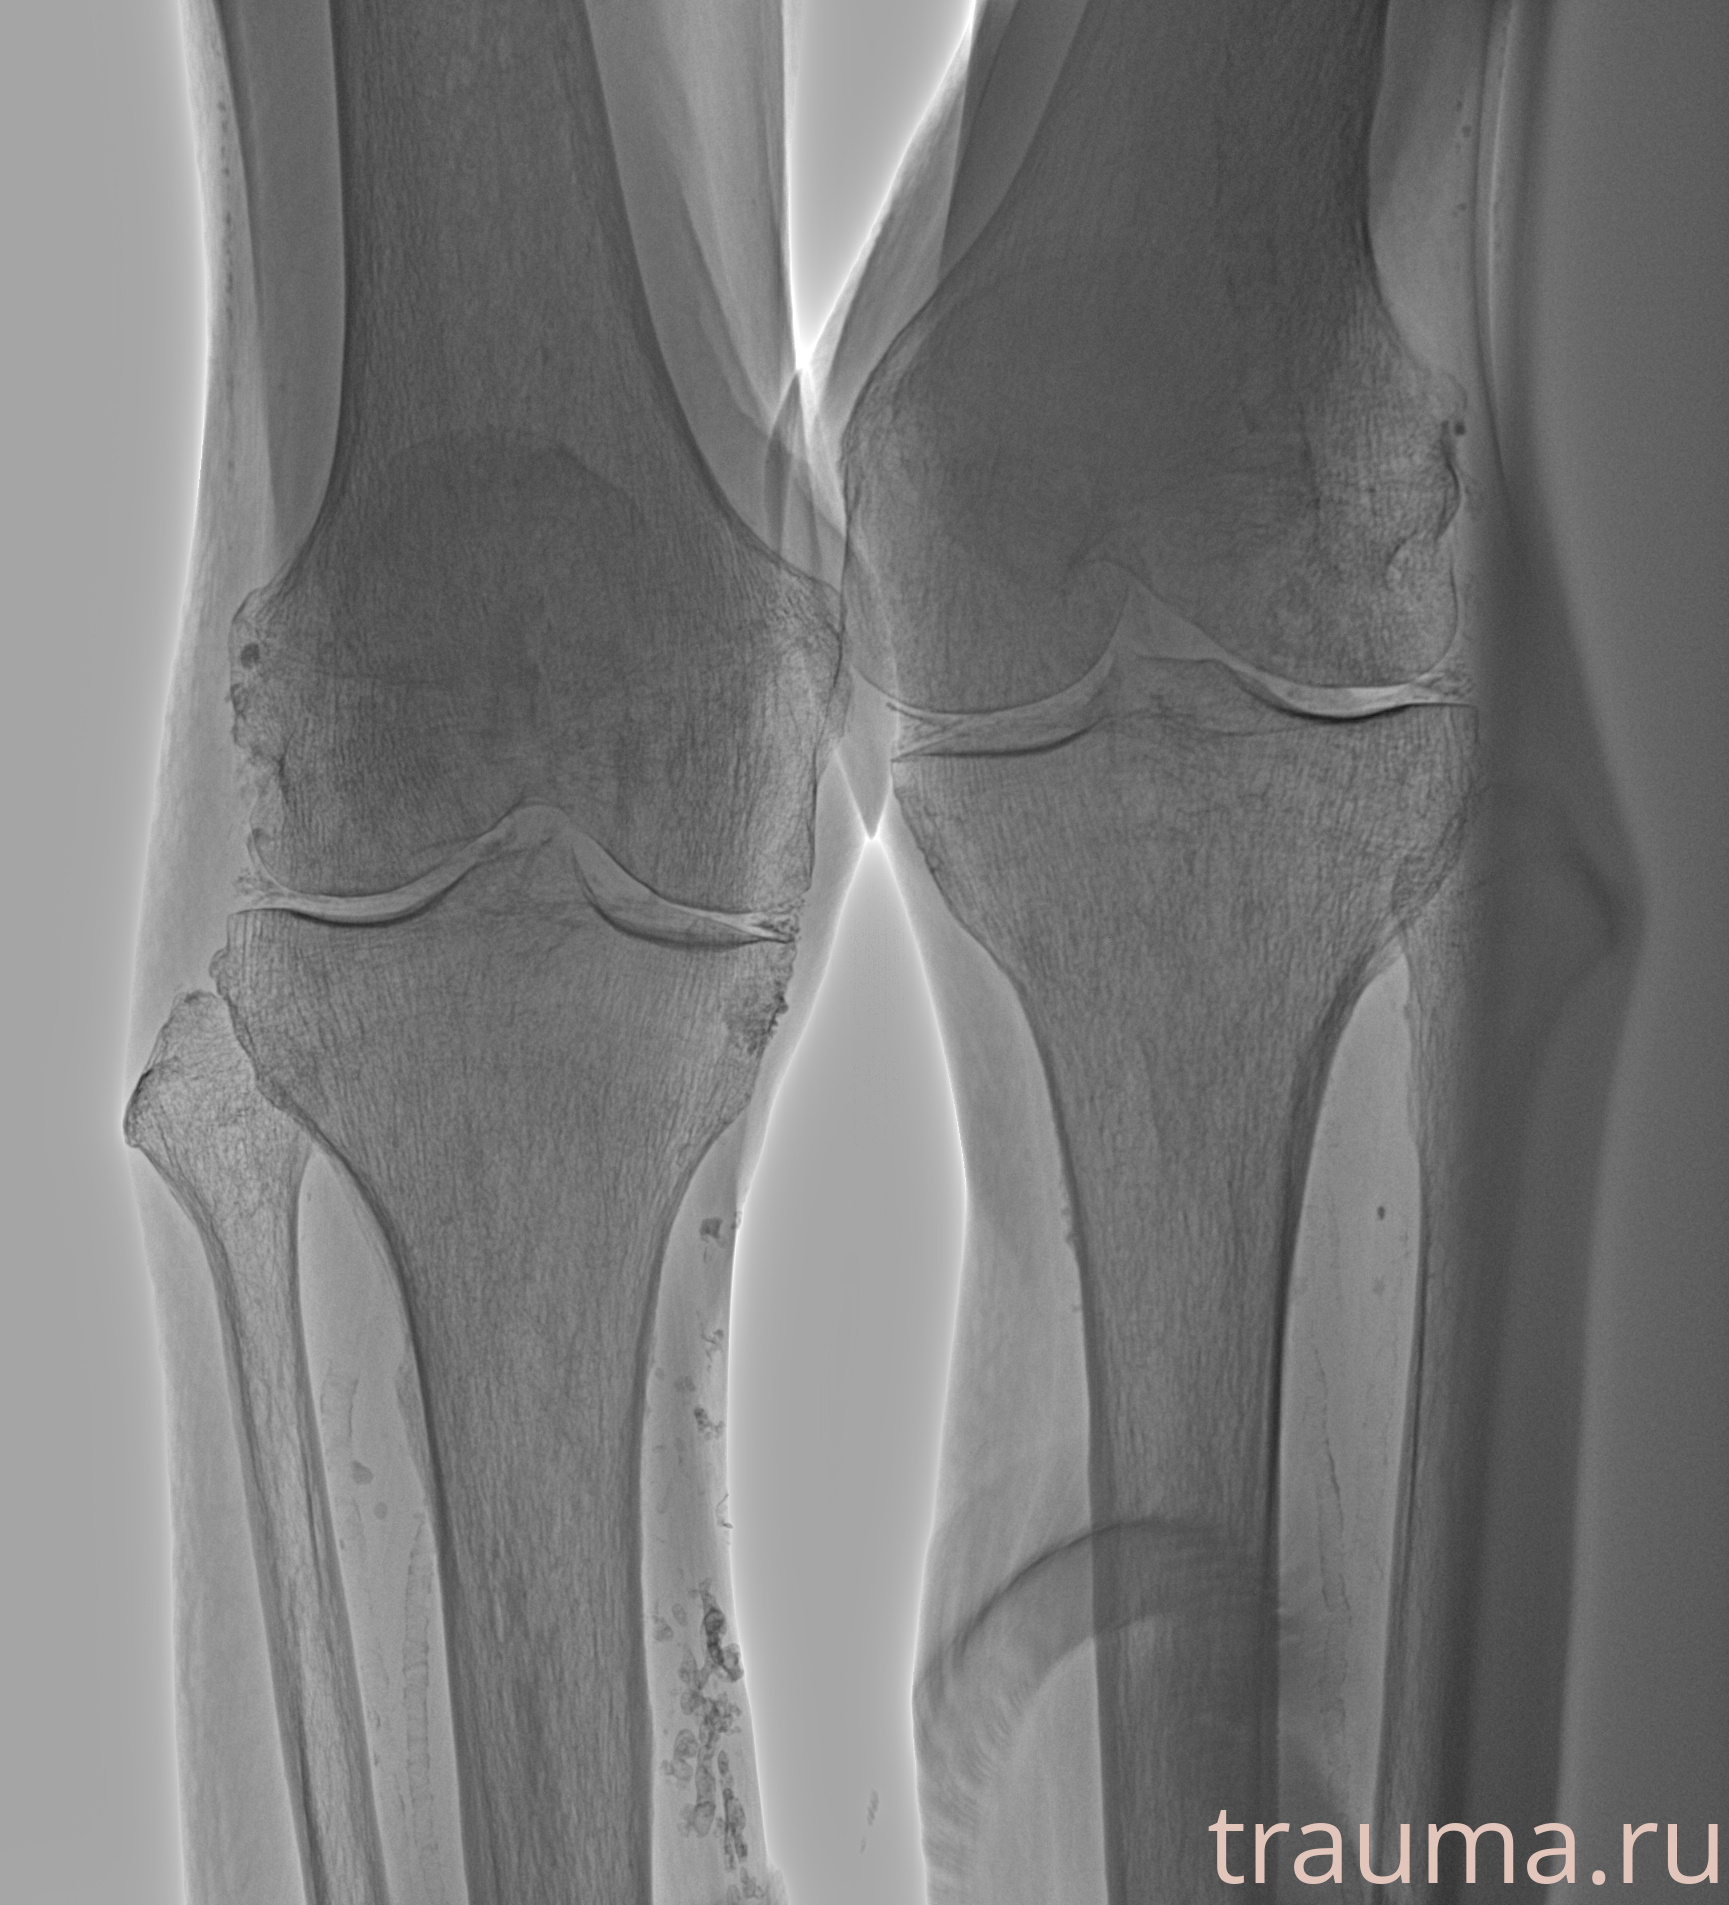

Рентген на дому: по вашему адресу приезжает врач-рентгенолог, травматолог-ортопед с мобильным рентгеновским аппаратом, проводит диагностику травмы или заболевания, делает необходимые рентгенограммы, дает рекомендации по дальнейшему лечению. Получить качественные снимки в домашних условиях возможно благодаря уникальной методике, разработанной МосРентген Центром для института  Склифосовского